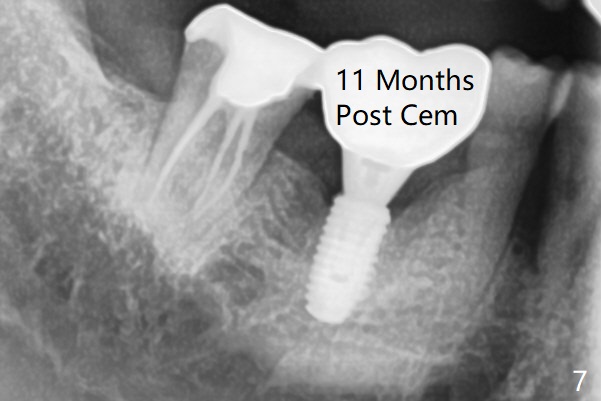

The sockets of #30 (M) of a smoker (M) are apparently not healing ~ 2 months post extraction (Fig.0, 0'). The ridge looks wide 3 months post extraction without bone graft in other office before (Fig.1) and after (Fig.2) flap surgery. The socket appears to have healed perfectly consi-dering buccal defect (M) revealed by CT ~ 1 month earlier. When a 5x10 mm implant is placed with guide and high torque (in spite of overprep), granu-lation tissue is found mesio-buccal (MB, Fig.2 *). After curettage, bone graft is placed around the implant, especially MB (Fig.3 *), followed by PRF. Periodontal dressing dislodged a few days postop because of mastication on the right side (Fig.4), whereas the anterior one (24/26) remains in place. There is a small gap around the implant when it is uncovered (Fig.5 arrowheads). It appears that some of bone graft gets lost from the incision (smoker). A 6.5x5.5(4) mm cemented abutment is seated and torqued at 30 Ncm before impression (Fig.6). There is no bone loss 11 months post cementation (Fig.7).